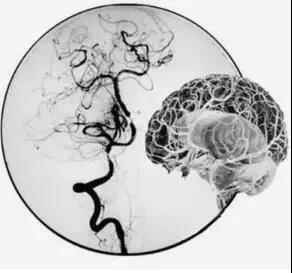

吴主任首先完善脑血管造影(DSA)检查,并详细结合CT、核磁共振检查以及患者右边大脑出现的如虫蛀般大大小小梗塞灶,最终判断疾病“元凶”是罕见的“烟雾病”。

烟雾病是一种进行性血管闭塞,由于患者主干血管闭塞,血液无法供应到大脑,小血管就会拼命扩张,扩张到极限状态,非常容易破裂,造成脑出血,很多患者也是因为出现脑出血才到医院就诊。

“正是因为重要血管无法正常工作,导致患者脑部‘催生’出很多新生异常血管,这些血管很细很密,在血管造影下,就像烟雾一般,因此被称为烟雾病。”吴主任介绍。

DSA脑血管造影发现患者右侧一根主干颈内动脉完全闭塞、对侧的颈内动脉也出现狭窄,这意味着供应脑部血液的四根主要血管,两根都有问题。此时的李女士右边大脑血供差,侧枝循环不理想,左边血管供血少,再发展下去,很可能出现大面积脑梗,如果再不及时采取措施,病情只会越来越重。治疗方法只有一种——“颅内外血管搭桥术”。